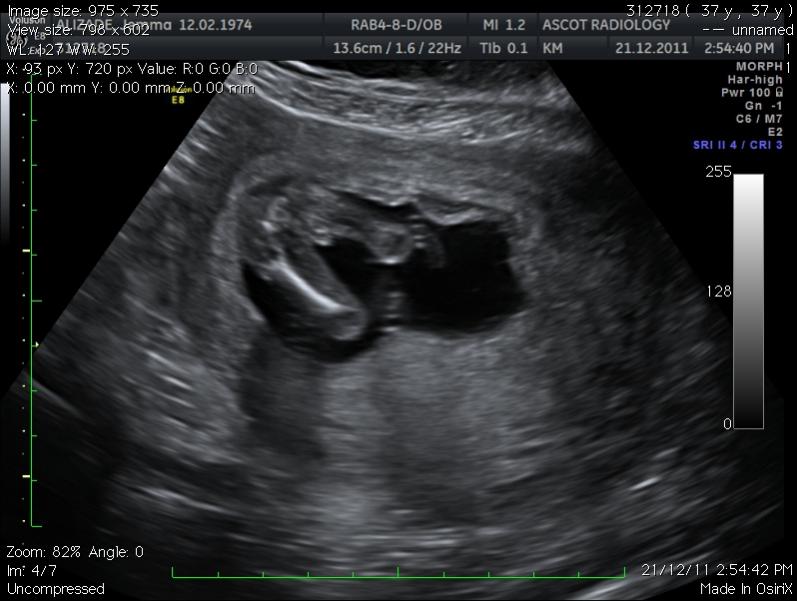

Hi, i am new here and i just can't work out my potty shot, can anyone help me - girl or boy?Attachment 992

The sonographer thought it was a boy - taken at 15 weeks 6 days...

It looks boy to me!

Looks like a boy to me.

That is a boy!

Could be a boy, but not the best pic to guess from. GL.